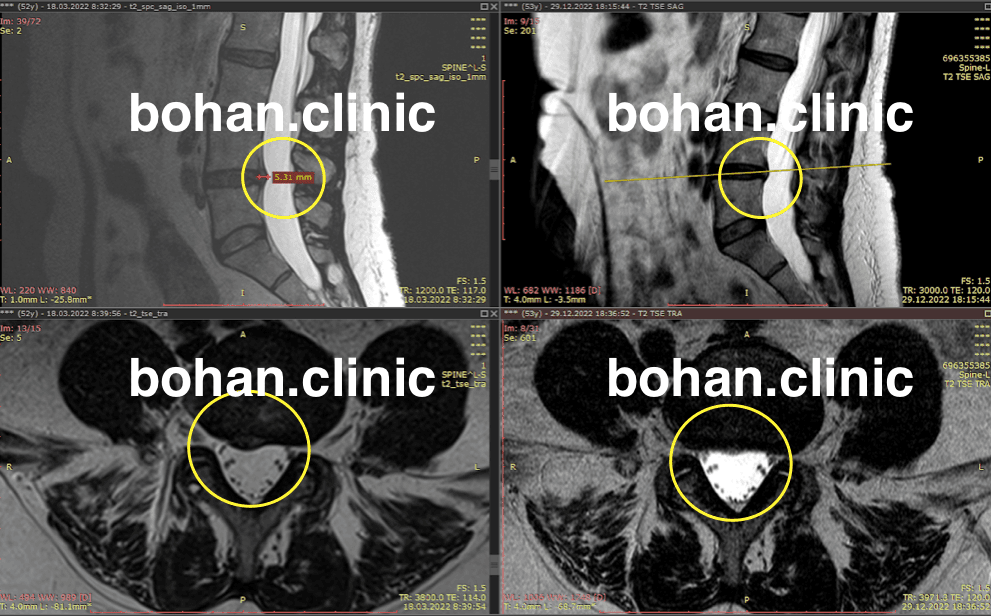

Метод лікування грижі шляхом стимуляції резорбції в Україні був впроваджений у 2020-2021 роках.  Алгоритм оцінки грижі на предмет резорбції, що використовується у клініках – є авторським, розроблений лікарем Боханом А.Ю.